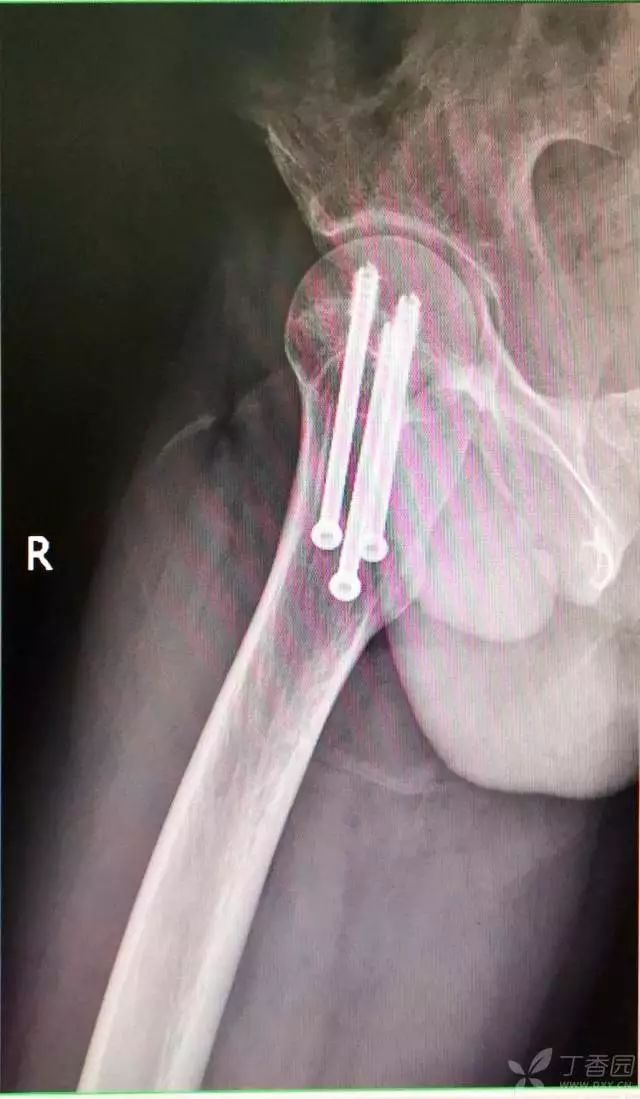

7. 摆 4 字位检查侧位导针的位置是否恰当

8. 最后测深依次拧入合适长度的螺钉

术后复查

术后十个月复查,骨折愈合,正常行走。